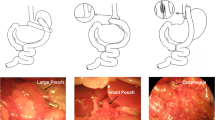

Surgical Procedures

After a 24-h fast, the rats were anesthetized with an intraperitoneal injection of 1% sodium pentobarbital solution (5 ml/kg). RYGB operations were initiated by a 4-cm midline incision. The stomach was divided 5 mm below the gastro-oesophageal junction from the lesser to greater curvature horizontally. The proximal stomach was closed by a 4-0 silk suture (Ningbo medical needle, China) in a simple interrupted suture technique to create a small gastric pouch, and the distal stomach was closed in a similar fashion. Then jejunum was transected 10 cm distal to the ligament of Treitz and the stump was ligated with a 4-0 silk suture. The distal limb of jejunum was brought up to the small gastric pouch, and a 7-mm incision was made on the antimesenteric border of the bowel wall and anterior gastric wall along with greater curvature, respectively. The distal limb of the jejunum was anastomosed to the small gastric pouch with a side-to-side gastrojejunostomy. The proximal limb of the jejunum carrying the biliopancreatic juices was reconnected downward to the Roux limb at a distance of 15 cm from the gastrojejunostomy with a side-to-side jejunojejunostomy. Both the gastrojejunostomy and jejunojejunostomy were performed in a simple interrupted varus suture technique with an about 7 mm of anastomosis using a 5-0 silk suture (Ningbo medical needle, China). Sham surgeries involved the same abdominal incisions and gastrointestinal transections as those in the RYGB group, and reanastomosis was performed at the same sites.